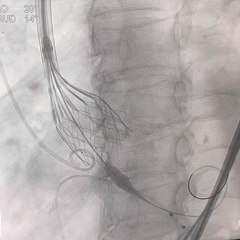

全展开造影,瓣膜位置较高

多体位造影,瓣膜位于瓣上

再次回收,第三次释放

全展开造影,大弯侧0位

左侧位造影,小弯侧深度可

脱钩后造影,瓣膜位置可